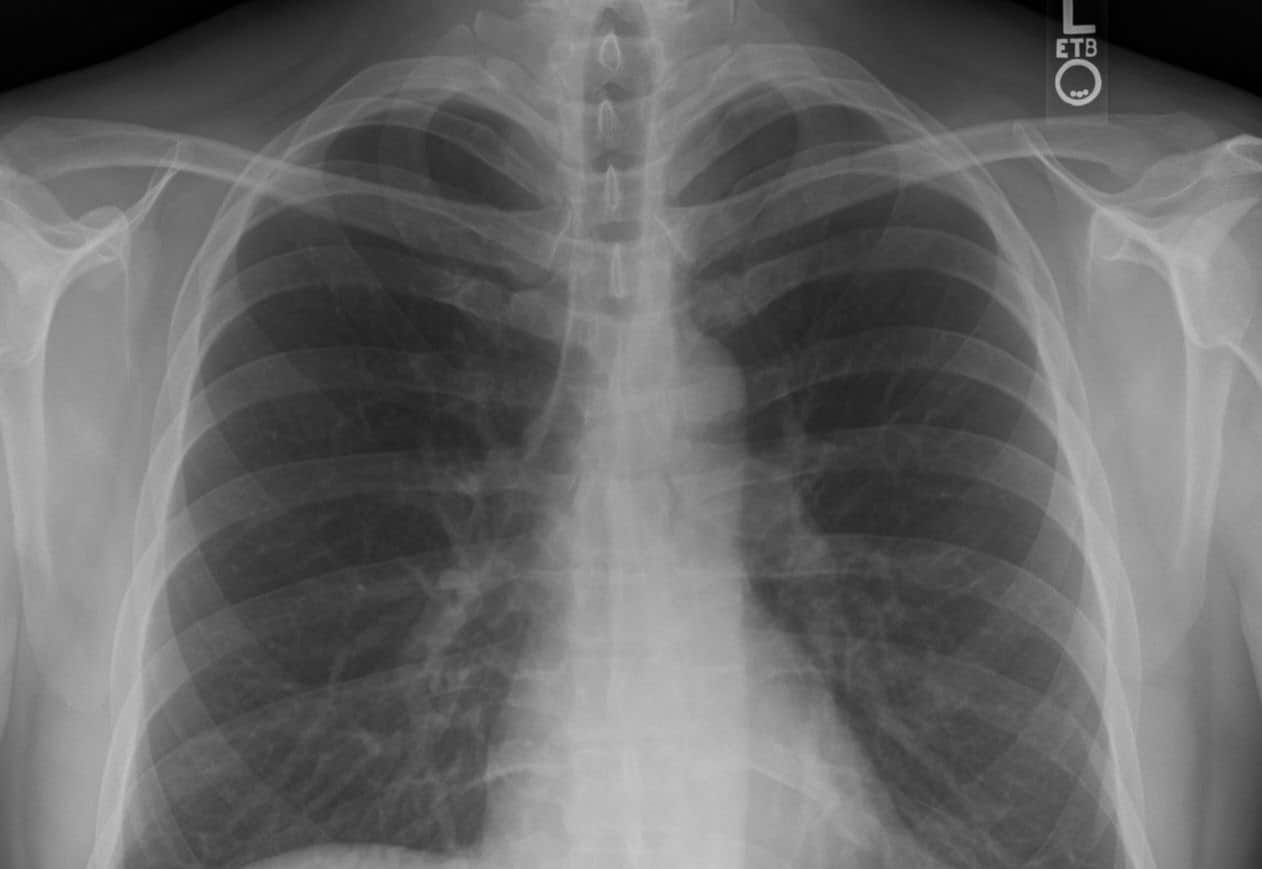

Во время пневмонии легкое может стать плотным как печень

Пневмония возникает, когда инфекция — бактерии, вирусы или грибки — преодолевает защитные барьеры дыхательных путей. Если местный иммунитет не справляется, микробы начинают размножаться в альвеолах.

В ответ иммунная система запускает мощную воспалительную реакцию: сосуды в легких расширяются, и альвеолы заполняются жидкостью, иммунными клетками и белком фибрином. Это приводит к «затоплению» дыхательных путей, в результате которого кислород перестает поступать в кровь, а углекислый газ не выводится наружу. Именно это состояние вызывает характерные симптомы — одышку, кашель и нехватку воздуха, а в тяжелых случаях может привести к дыхательной недостаточности.

Как объяснил Олег Долгих, одна из стадий крупозной пневмонии, которая в отличие от очаговой затрагивает сразу целую долю легкого, называется красное опеченение. При нем часть жидкости и эритроцитов из мелких сосудов заполняют альвеолы. Пораженная часть легкого становится плотной и похожей на ткань печени. Внутри легочных мешочков скапливается упомянутое ранее клейкое вещество фибрин, которое и придает плотность ткани.

Это состояние не только блокирует доступ кислорода, но и создает идеальную среду для размножения бактерий, усиливая воспалительную реакцию.